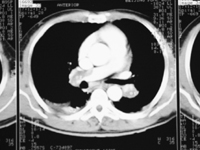

增强CT显示肺动脉内充盈缺损(图1),2例位于肺动脉主干,9例分别位于左侧和右侧肺动脉干;同位素血流灌注扫描显示相应部位肺灌注缺失;肺动脉造影提示相应部位肺动脉不显影或显影延迟(图2);超声心动图估测肺动脉收缩压为9.3~11.3kPa,肺动脉瓣和三尖瓣反流,右心增大,室间隔反向运动。5例术前放置下腔静脉滤网。患者不吸氧动脉血氧饱和度(SaO2)为0.85~0.9动脉氧分压(PaO2)均<8 kPa;术前纽约心脏学会(NYHA)心功能分级Ⅱ级3例,Ⅲ级6例,Ⅳ级3例。